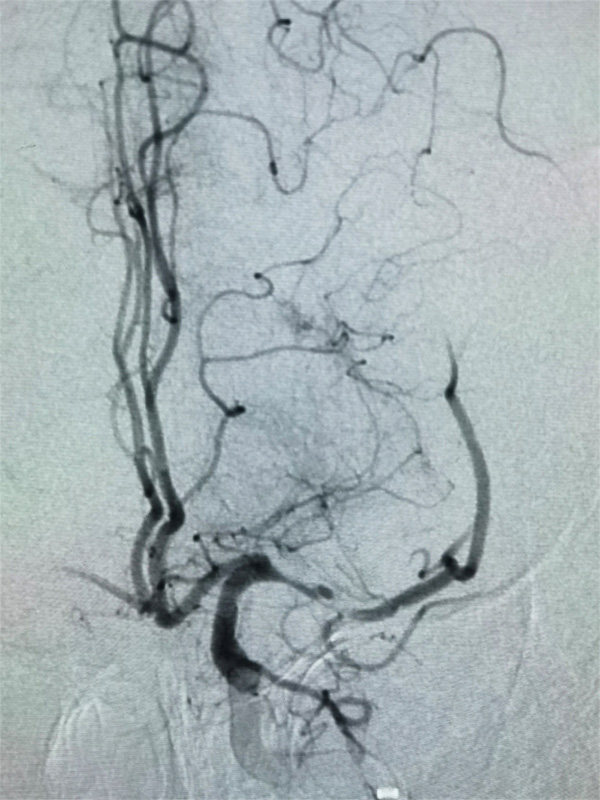

22:30,手术准时开始。柴尔青教授现场指导,巴特尔医生和沈寻医生迅速消毒、铺台、穿刺、接造影导管。术中判断患者是2型主动脉弓,血管硬化严重,超选左侧颈动脉,清楚的显示了病灶,左侧大脑中动脉的闭塞,这需要全麻下才能完成进一步的取栓操作,并且要求麻醉过程中血压要维持在140/80mmHg左右。技术娴熟的麻醉师给药、插管、麻醉,15分钟完成了全部操作,而且血压完全平稳没有波动。

时间一分一秒地飞过,手术按方案顺利推进。取栓导管顺利的通过闭塞血管,取栓支架释放后即带出来了血栓。即刻造影,左侧大脑中动脉血流恢复,远端血管显影,由此发现了发病病因是左大脑中动脉的斑块形成造成管腔重度狭窄(狭窄约99%)后,小血栓的形成又突然把血管完全堵死了,如果不处理血管狭窄,此处会再次发生闭塞,紧急启动备用方案---球扩血管成型,将大脑中动脉狭窄程度缓解了80%左右,瞬间血流完全通畅了,继续观察半小时左右,血流很稳定,宣布手术结束。这时时钟显示为凌晨01:35。从发病到入院,到罪犯血管开通,全程仅仅4个半小时。参与手术的所有医护人员,打赢了这场漂亮的攻坚战。可以很自信地说,在国际标准的溶栓时间窗内顺利完成了颅内血管取栓和开通任务,这也真实体现出了国家应急医学研究中心卒中团队的救治效率和临床经验。

大脑中动脉急性闭塞和血流中断

大脑中动脉术后完全开通以及脑血流恢复